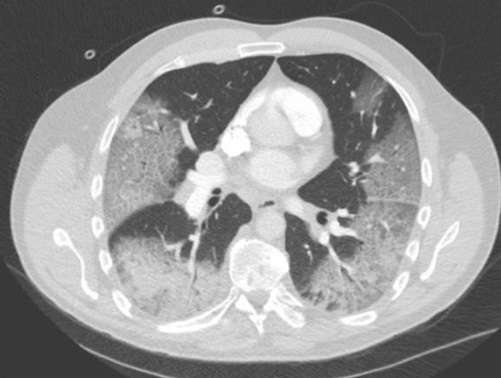

13

Q

¿Cuál es el diagnóstico?

A

Consolidación vidrio esmerilado y empedrado loco.